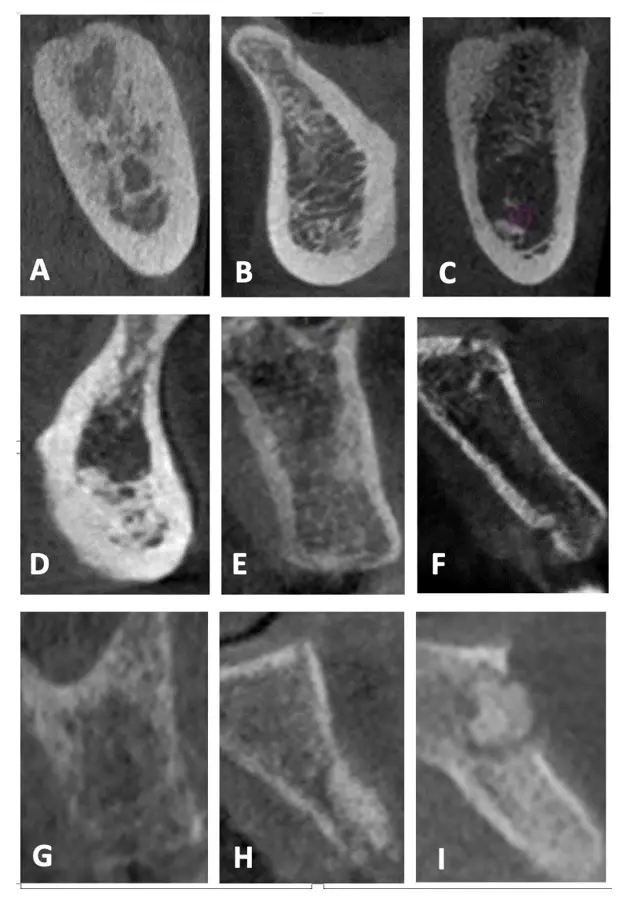

Durante años, se establecieron las propiedades biomecánicas del hueso basándose únicamente en medidas a gran escala, pudiendo diferenciarse entre el hueso trabecular y el hueso cortical. Sin embargo, actualmente es posible un mayor análisis a nivel micrométrico que permite explorar entre los componentes orgánicos, tisulares, celular y moleculares. Es así que gracias a aproximaciones nanoestructurales se muestran asociaciones entre las propiedades biomecánicas y las calidades óseas, las que se pueden presentar tanto en el hueso cortical como en el trabecular de manera indistinta. En el cortical, el espacio poroso ocupa el 5-10%, mientras que en el trabecular se encuentra en el 30-90% del total de la estructura9 (Figura 1).

Los esquemas clásicos de clasificación se basan en la proporción relativa que existe entre el hueso cortical compacto y el hueso trabecular esponjoso.10,11 El hueso tipo I se considera el menos vascular y más homogéneo, el tipo II es una combinación de hueso cortical con cavidades medulares, el tipo III está predominantemente compuesto de hueso trabecular, y el tipo IV se describe como una corteza muy delgada con trabéculas de baja densidad.12 Incluso se han propuesto diferentes analogías entre los tipos de huesos y los tipos de madera; que van desde la madera tipo balsa hasta la tipo roble.13 Posteriormente, siguieron surgiendo clasificaciones utilizando el criterio cuantitativo;14 sin embargo, su valor diagnóstico sigue siendo cuestionable.15,16

Calidad ósea según la clasificación de Lekholm y Zarb (Figura 2).

- Tipo I: hueso compacto completamente homogéneo.

- Tipo II: capa gruesa de hueso compacto rodeando al hueso trabecular denso.

- Tipo III: capa delgada de hueso compacto rodeando al hueso trabecular denso.

- Tipo IV: capa delgada de hueso compacto rodeando al hueso trabecular poco denso.